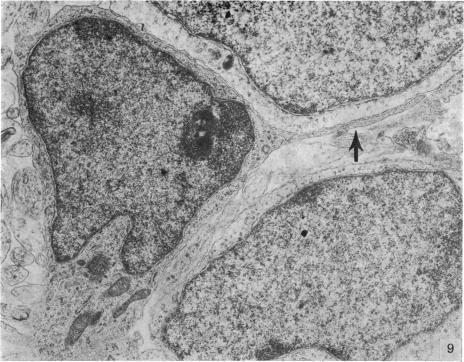

Five coronal levels of the arcuate nuclei in newborn male and female rats were examined with the transmission electron microscope. The nuclei from male and female neonates appear similar in all respects. All levels exhibit a significant population of round to oval cell profiles with large centrally located nuclei and scant cytoplasm which contains predominantly ribosomes, sparse mitochondria, and a few short cisternae of rough endoplasmic reticulum. These organelle-poor cell profiles resemble neuroblasts in other parts of the developing CNS. The arcuate nuclei of neonates also exhibit some cell profiles with the variety and quantity of organelles characteristic of mature neurons in the arcuate nuclei of adult rats. In addition, the neonatal arcuate nuclei show a paucity of synapses with apparent immaturity of those present, and numerous structures identified as growth cones. Definitive macroglia are not present in the arcuate nuclei of newborn rats.

用透射电子显微镜检查了新生雄性和雌性大鼠弓状核的五个冠状层面。雄性和雌性新生大鼠的细胞核在各方面看起来都相似。所有层面均显示出大量圆形至椭圆形的细胞轮廓,细胞核位于中央且较大,细胞质稀少,主要含有核糖体、稀疏的线粒体和一些短的粗面内质网池。这些细胞器较少的细胞轮廓类似于发育中的中枢神经系统其他部位的神经母细胞。新生大鼠的弓状核还显示出一些细胞轮廓,其细胞器的种类和数量具有成年大鼠弓状核中成熟神经元的特征。此外,新生弓状核的突触较少,且现有的突触明显不成熟,还有许多被鉴定为生长锥的结构。新生大鼠的弓状核中不存在明确的大胶质细胞。